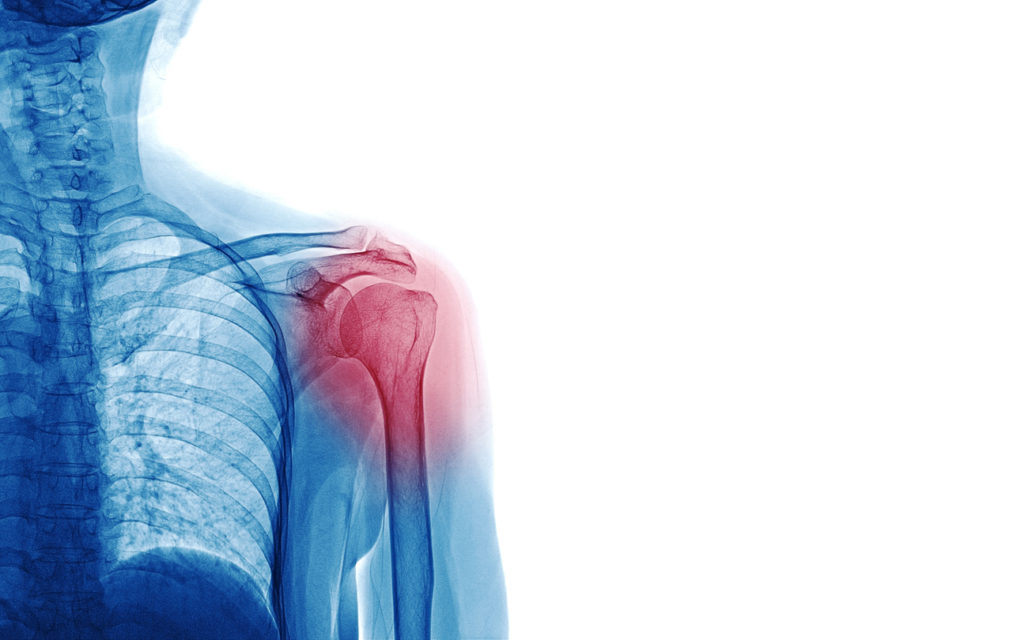

A dislocated shoulder is the result of the head of the upper arm (the humerus) becoming either partially or fully dislodged from the glenoid socket. A very common injury amongst athletes — especially those who participate in contact sports like football, soccer and gymnastics, each of which can result blunt force trauma – a shoulder dislocation can also be the result of falls, collisions and car accidents. Dislocations can also occur over time as the result of repetitive motions one might find in tennis, golf, and swimming; or due to one’s occupation, particularly those that require repetitive motions as found in painting, construction work and lifting.

Once you are seen, expect your orthopedist to examine the site and order imaging to ensure a complete and accurate picture of the dislocation, which may include other damage that might have occurred. If the injury is determined to be a dislocation with no other concerns, your orthopedist likely will perform reduction – a non-surgical technique in which he will manually manipulate the ball of your shoulder back into the socket. You should feel immediate relief from pain once the shoulder bone and collarbone are back in the proper position.